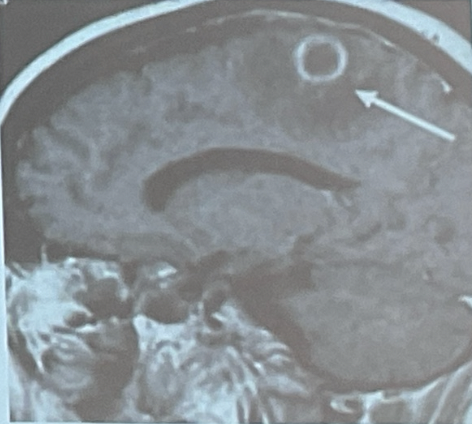

Colección focal dentro del parénquima cerebral, que puede surgir como una complicación de una variedad de infecciones, trauma o qx.

Diagnóstico

A

Puede tener presentación sutil

Puede salir normal LCR

Se hace biopsia para drenar contenido